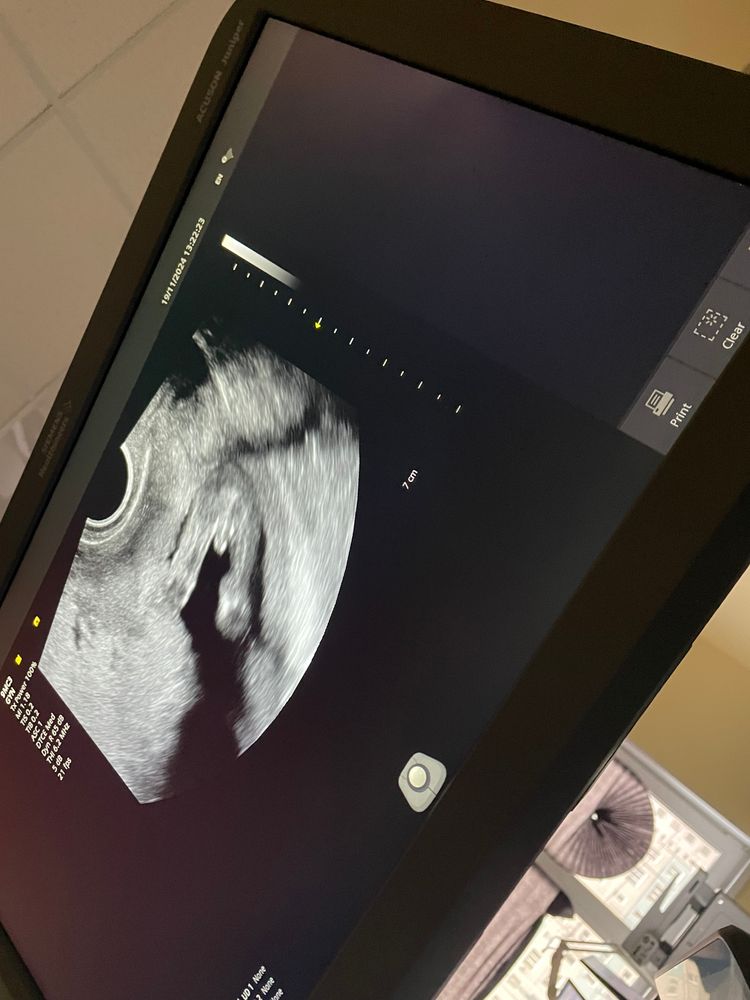

Пол ребенка на 15 неделе

А мне кажется, что девочка (три складки есть), а торчит пуповина...

Мальчик. Поздравляю.)

Ахаха, так четко показал свои причиндалы☺️ мальчишка у вас.

Похоже что мальчик 😄

Это мальчик

Определение Пола по половому бугорку Это мальчик же?:) 17,2 срок на этом фото